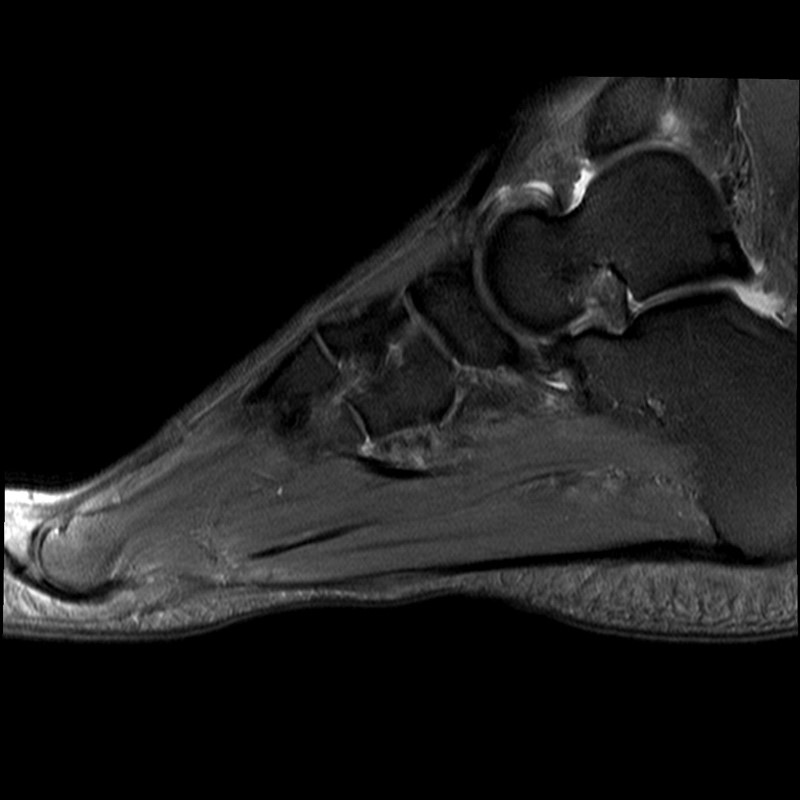

Abb. 9a–d: chron. Plantarfasziitis mit plantarem Fersensporn und Irritation Baxternerv plantar lateral

Kasuistik: 28-jähriger Patient, Profisportler.

Abb. 9a: Plantarer Fersensporn und Plantarfasziitis im MRT prä-op.

Abb. 9b: Plantarer Fersensporn im CT prä-op.

Abb. 9c: Lateraler Zugangsweg bei atypisch weit nach plantar lateral liegendem Sporn.

Abb. 9d: Röntgenkontrolle nach Minioffenem Plantarfaszienrelease und Abtragung Fersensporn mit Neurolyse.

Zum Lesen der Bildbeschreibung und zur Vollansicht bitte die Bilder anklicken. Bilder: Manfred Thomas.